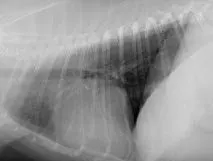

High-quality, 3-view thoracic films that are correctly positioned should be the starting point for all practitioners. For best results, the practitioner should be actively involved in processing the images to ensure correct anatomical positioning and exposure (Figure 1). Whenever possible, more than 1 person should review films for abnormalities and roentgen changes.

Expiratory (A) and inspiratory (B) right lateral radiographs from a 7-year-old neutered male poodle. Because the act of respiration changes the thoracic appearance, inspiratory films should be attempted to distinguish artifacts from true lung pathology.